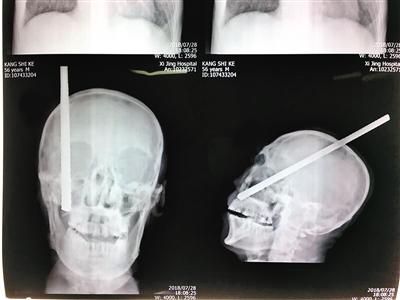

小康的父亲康杰(化名)今年56岁。7月28日上午,他正在甘肃一家工地干活时,不慎被一根长3米从高处坠落的钢筋刺入头部。康师傅当场倒地,意识出现障碍,逐渐进入昏迷状态。钢筋造成的伤势严重,自头顶部经右侧大脑半球贯穿至右侧面部颅底穿出,从面部皮下可触及钢筋头部。

由于钢筋太长,无法将患者抬进120救护车,在现场紧急抢救处理中,消防队员用液压剪将钢筋局部截断,保留了约30厘米长钢筋,其中约20厘米存留在颅内。患者被紧急送至当地医院做了头颅CT等检查后,考虑到病情复杂,风险极高,甘肃当地医院建议转至西安的西京医院进一步诊治。

钢筋刺入患者头部的影像 (医院供图)